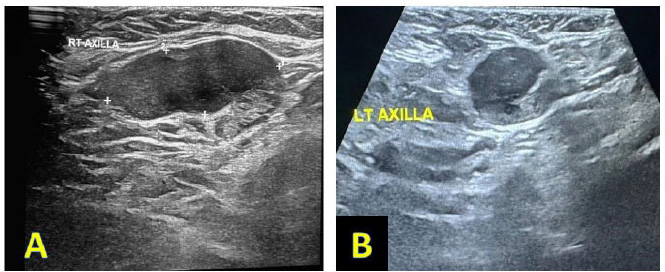

Fig. (5).

Ultrasound examination of the right (A) and left (B) axillary regions showed enlarged axillary LN being round to oval in shape; most of it showed efface distorted hilum, thick cortex being about 7-8 mm in size, with the largest one measuring about 24x17 mm, 21 x 16 mm. All of these findings were suspicious of pathological LN and fine needle aspiration (FNA) from both axillary regions.